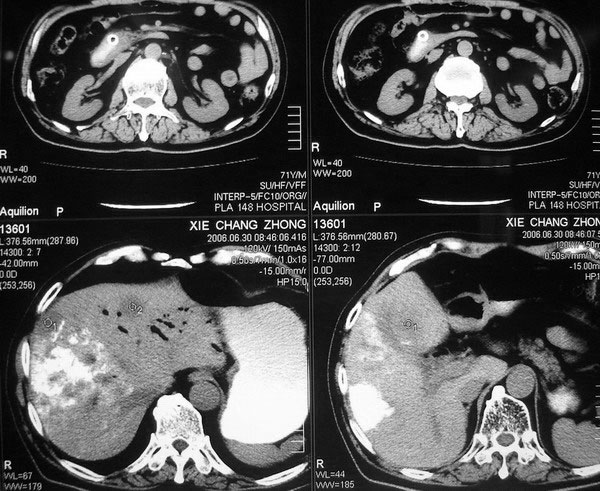

以下是引用逸风在2006-8-26 17:37:00的发言:[br]ct显示:\"壶腹癌肝转移\"行介入碘油栓塞术及胆总管内支架植入术后,肝右叶斑片状高密度碘油弥散,肝左叶见多个结节样低密度病灶,边缘清晰,肝左叶肝内胆管内气体影聚集.胆总管通常,腹膜后未见明显淋巴结肿大,片内所见其他未见明显异常.[br]诊断:1.壶腹癌肝转移\"行介入碘油栓塞术及胆总管内支架植入术后改变;2.肝左叶转移瘤,请与原片对比观察.